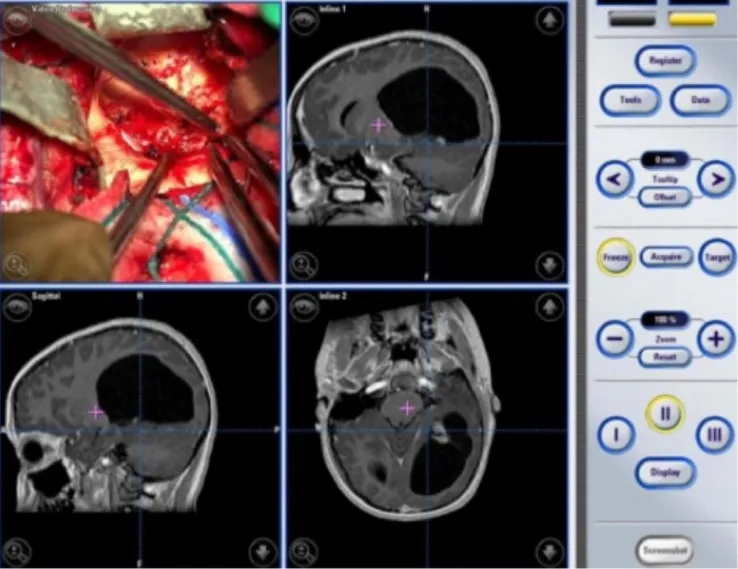

(艾文的左枕叶毛细胞性星形细胞瘤术中影像分析)

经过James T.Rutka教授手术团队的讨论,他们决定对艾文使用无框架立体定向术和术中神经导航手术,以确保他的病变完全切除。,手术结果得偿所愿,全切除也意味着良好的预后。

一家人找到国际儿童脑瘤教授INC Rutka教授,Rutka教授与Jimmy及其家属进行了深入沟通,教授认为Jimmy的残余肿瘤不足3cm,适合采用一项微创技术——激光间质热疗(LITT)来消融病变。教授表示术后Jimmy可以很快出院,不会影响正常的学习和生活,与Jimmy一家达成共识后,教授立即为其制定了周详的微创治疗方案。由于Rutka教授团队对于整个LITT技术已经有丰富的经验,Jimmy的手术很成功。